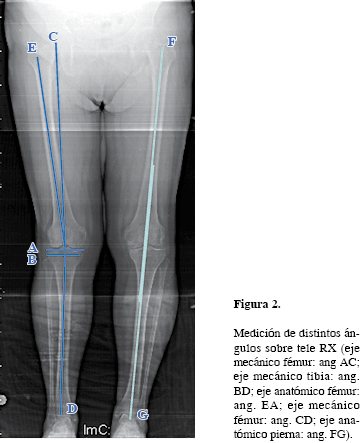

Moldes Individualizados Para Alineacion De La Artroplastia Primaria De Rodilla